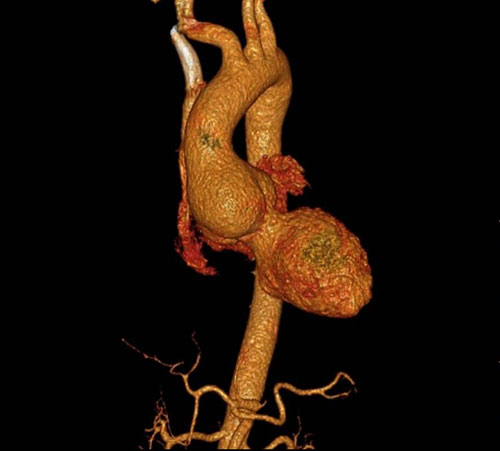

病例一:小切口成功救治主动脉瓣关闭不全合并主动脉窦动脉瘤患者

第一例患者为一名60岁男性,因活动后经常出现头晕、胸闷,前来我院就诊。经检查确诊为重度主动脉瓣关闭不全合并主动脉窦动脉瘤。正常人的胸主动脉直径在4cm以下,而该患者动脉瘤最大直径达7cm,随时可能发生动脉瘤破裂威胁生命。由于对传统开胸手术的巨大创伤感到恐惧,患者多次就医未能接受手术治疗。最终,他选择来到我院接受李欣医生的治疗。

术前主动脉CTA

在充分的术前准备后,李欣和杨珏医生采用微创手术技术,仅通过胸骨上段5.5cm的小切口,为患者成功实施了包括主动脉瓣机械瓣膜置换术、主动脉根部置换术及冠状动脉开口重建术在内的Bentall手术。手术过程顺利,术后患者恢复迅速。仅3小时后便拔除气管插管,术后24小时引流量100ml,术后第1天顺利转入普通病房,4天后即可出院。与传统Bentall手术平均8天住院时间相比,患者的恢复时间明显缩短,且胸前的手术瘢痕长度仅为传统手术的四分之一。